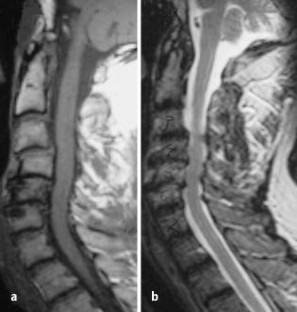

Eine Einengung des Spinalkanals ließ sich sowohl in der CTM als auch MRT darstellen. Bezüglich des Ausmaßes der Spinalkanaleinengung bestand zwischen den T1w-axialen Bildern und den Postmyelo-CT-Bildern kein signifikanter Unterschied.

Disc herniation could be depicted in CTM as well as in MRI. The extent of herniation did not differ between CTM and T1w. The extent of herniation seemed higher on T2w than on T1w (p <0.001). Foraminal encroachment was easier to diagnose in CTM. When regarding transverse T1w and T2w images simultaneously, a missing root in MRI corresponded to a missing root in CTM and conventional myelography and vice versa. Our data demonstrated the relative inability of MRI to determine whether the compression is by soft tissue or bony structures.

Abb. 3a,b